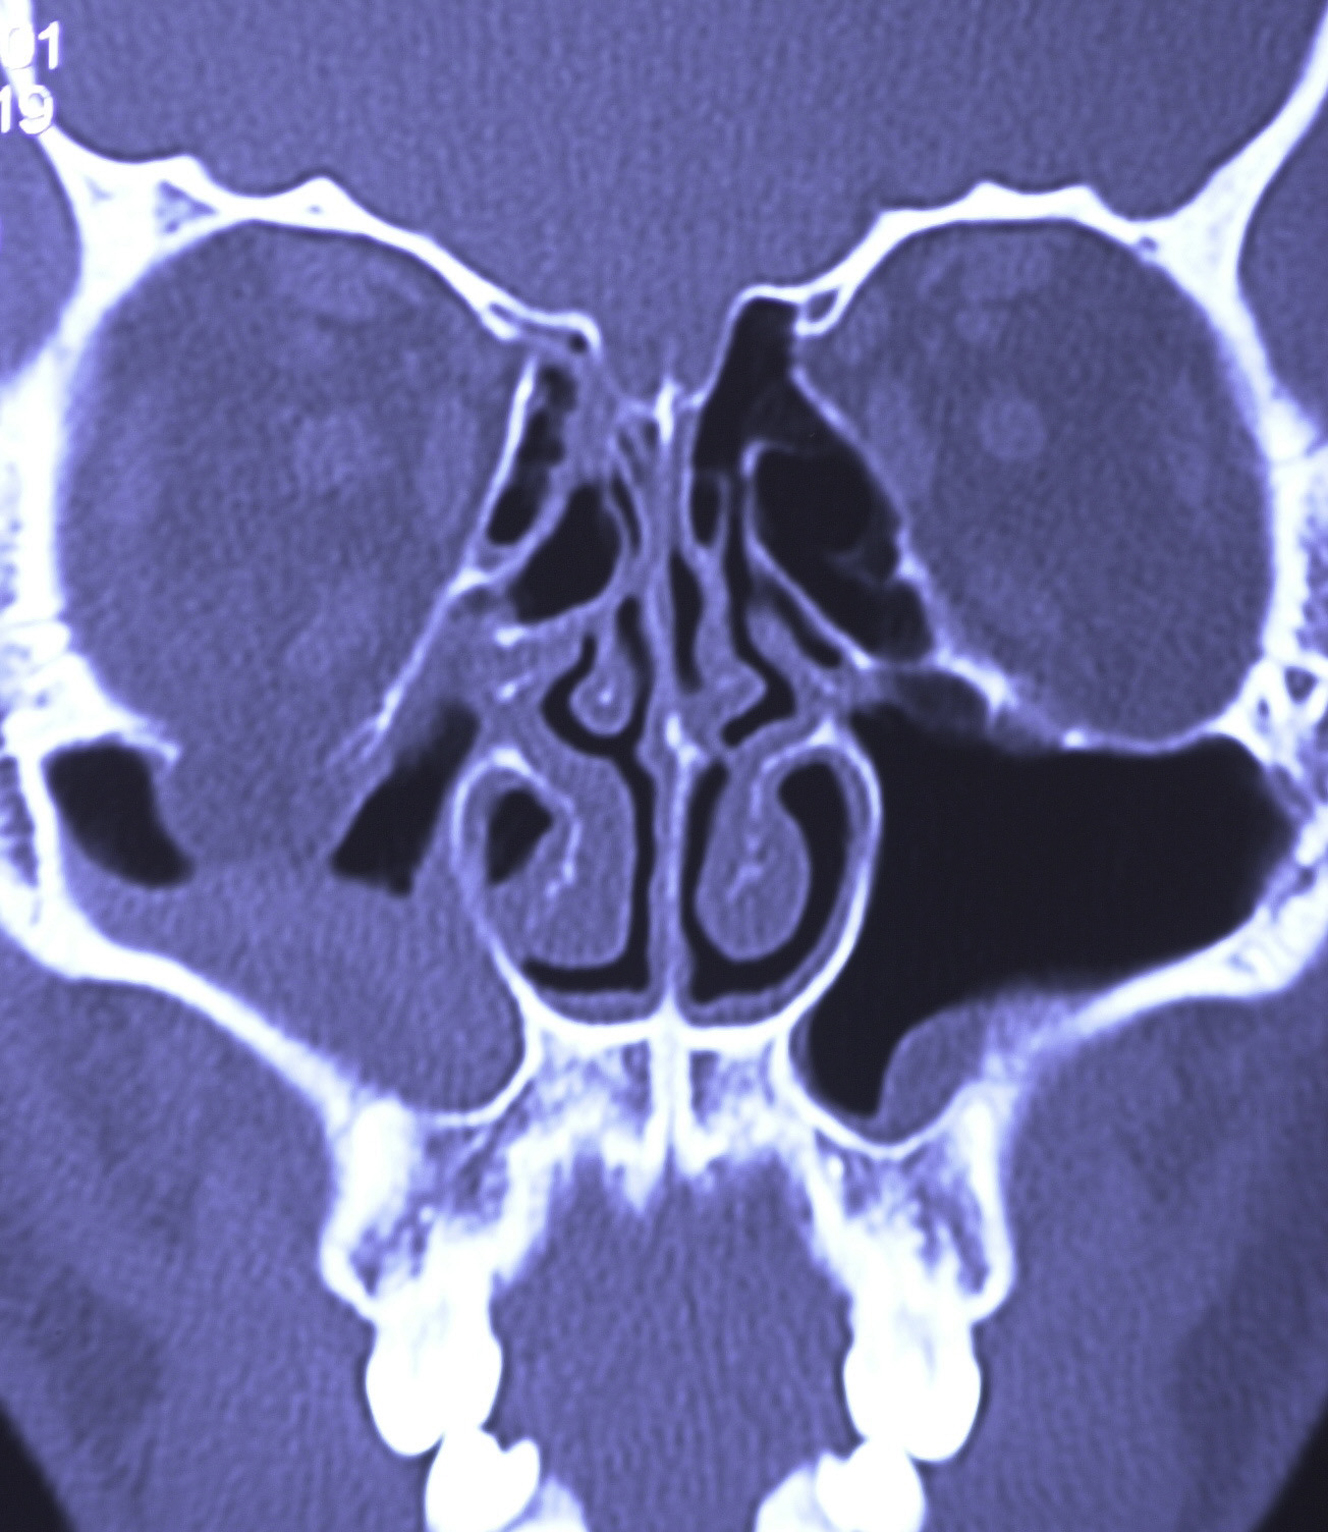

The mainstay of diagnostic testing after orbital trauma is radiological evaluation. Computed tomography (CT) imaging is the gold standard for evaluation of the bony orbit. Fine cuts (<2 mm) should be performed to achieve optimal evaluation of the orbital bone. CT imaging should be thoroughly evaluated in multiple planes. The coronal plane helps identify medial wall fractures as well as orbital floor fractures ( Fig. 2 ). Inferior entrapment may demonstrate a rounded or vertically oriented ovoid shape to the inferior rectus muscle. In addition, inferior rectus rounding may occur during disruption of the fascial sling which supports the orbit. The sagittal plane can aid in understanding the depth and length of an orbital floor fracture.